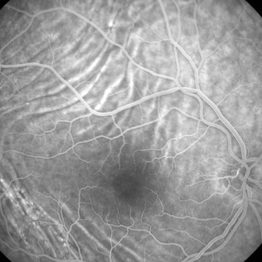

Idiopathic Choroidal Folds - Fluorescein Angiogram Idiopathic Choroidal Folds - Fluorescein AngiogramJan 11 2013 by Gerardo Garcia-Aguirre, MD Fluorescein Angiogram showing choroidal folds. Imaging device: Zeiss FF4 Condition/keywords: choroidal folds

Choroidal Folds - Fluorescein Angiogram Choroidal Folds - Fluorescein AngiogramJan 11 2013 by Gerardo Garcia-Aguirre, MD Fluorescein angiogram. Photographer: Gerardo Garcia-Aguirre, MD Imaging device: Zeiss FF4 Condition/keywords: choroidal folds